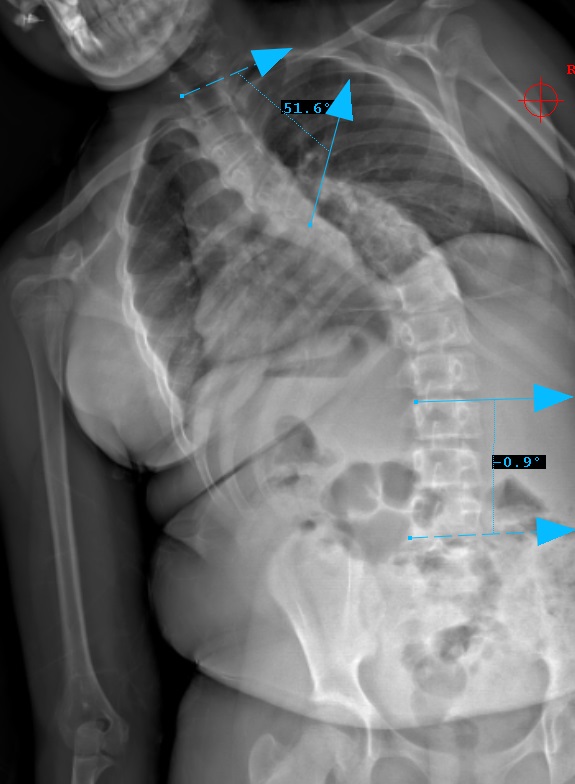

Preop LEFT Bend

Preop RIGHT Bend